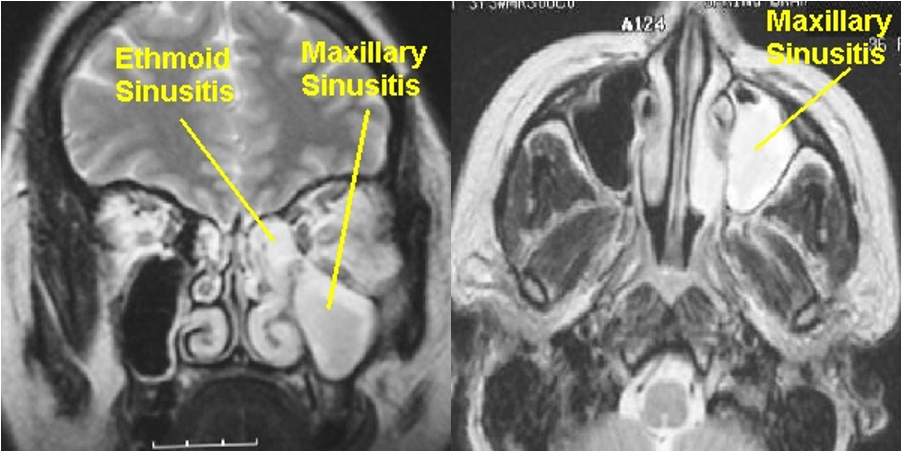

MRI

Tumor, infections, pain - not in first line such CT scan